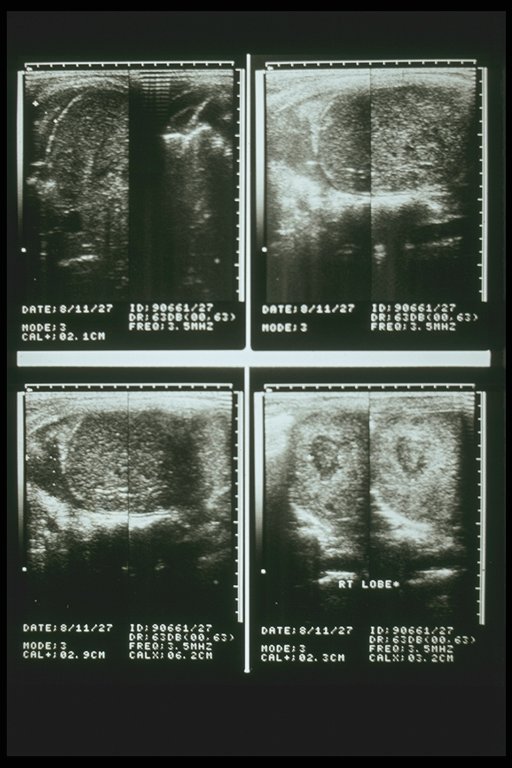

Subcapsular hematoma of the right lobe liver demonstrated by ultrasonography, a low echoic area is characteristic finding

Intrahepatic hematoma of the right lobe liver demonstrated by ultrasonography